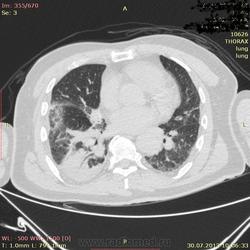

кт грудной клетки

Нужна помощь.Больной 77 лет госпит-н в хир отд. с диагнозом ЖКБ.Больному стало хуже стали беспокоять одышк. чувство нехватка воздуха.

ОАК лейк 18.СОЭ 30 мм\ч.Ваше мнение.Терапвет зак Внеболь правсторон. пневмония.Торак .хирург Синдром средний доли ?Рек - но сдать анализ  на ТБС, КТ грудн.клетки.

Пневмония, гидроторакс. Почему не начали с рентгенографии?

На Рентгене инфильтративная тень н/доли справа с четкими ровными контурами

Инфаркт-пневмония при ТЭЛА в диф.ряд. Хотя ЛА и не показана, всё вполне подходит.

Внезапно возникшая одышка в послеоперационном периоде всегда подозрительна на ТЭЛА плюс треугольная тень на рентгенограмме с ровными, четкими контурами. Надо искать эмболы в легочных артериях (кстати, оптимальная отсрочка после введения контраста - 20сек). Ясно также, что синдром средней доли тут никаким боком.

Предположительно: ТЭЛА. Данные полного КТ-исследования с внутривенным болюсным контрастированием помогли бы в диагностике.